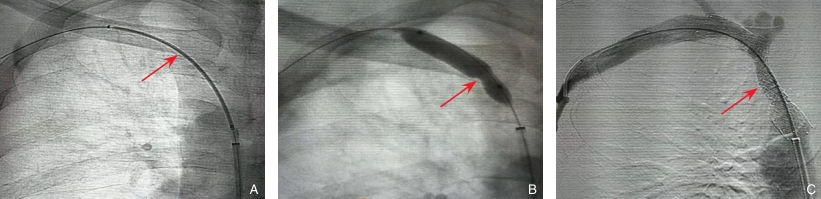

图2 经股静脉入路联合患侧IUEHA静脉入路处理右锁骨下静脉(subclavian vein,SCV)闭塞的BVA操作步骤 A:导丝通过右SCV;B:PTA;C:PTS后造影显示血流通畅恢复Fig.2 BVA via the femoral vein combined with ipsilateral IUEHA for right subclavian vein (SCV) occlusion A: Guidewire passage through the right SCV; B: PTA; C: Angiography after PTS showing restoration of blood flow